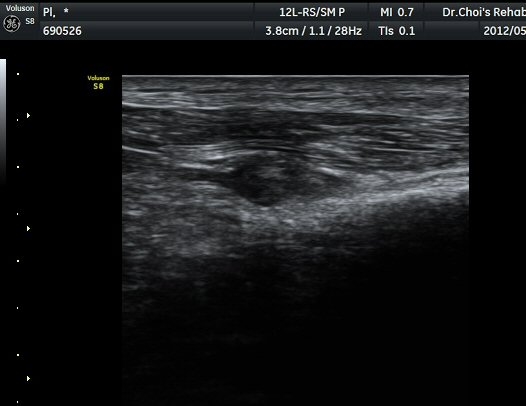

ŽÃËÀÚ¸¦ ´õ ¾Æ·¡·Î À̵¿ÇÏ´Ï Ãµºñ°ñ½Å°æÀÌ Àú¿¡ÄÚ µÕ±Ù µ¢¾î¸®·Î °üÂûµÇ´Ù°¡ ´Ù½Ã Á¤»óÀûÀÎ ¸ð½ÀÀ¸·Î °üÂûµÈ´Ù(±×¸² 7, 8).